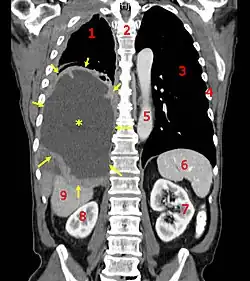

![]() | |

| A coronal CT scan showing a malignant mesothelioma Legend: → tumor ←, ✱ central pleural effusion, 1 & 3 lungs, 2 spine, 4 ribs, 5 aorta, 6 spleen, 7 & 8 kidneys, 9 liver | |